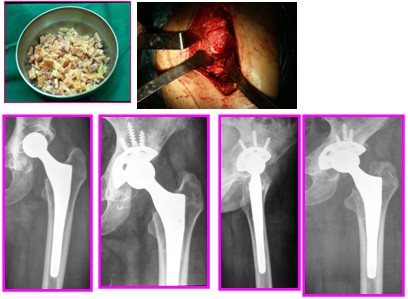

PaproskyⅣ型股骨骨缺损:广泛的股骨骨缺损,皮质骨边变薄,髓腔增宽。翻修时需采用皮质骨板捆绑重建股骨皮质完整性,髓腔内打压植骨,置入加长锥形抛光骨水泥柄。

2、股骨骨缺损修复

(1).颗粒植骨+非骨水泥柄

(2).髓内打压植骨+非骨水泥柄或骨水泥柄

(3).结构植骨+颗粒植骨+非骨水泥柄或骨水泥柄

非骨水泥柄包括组合式柄